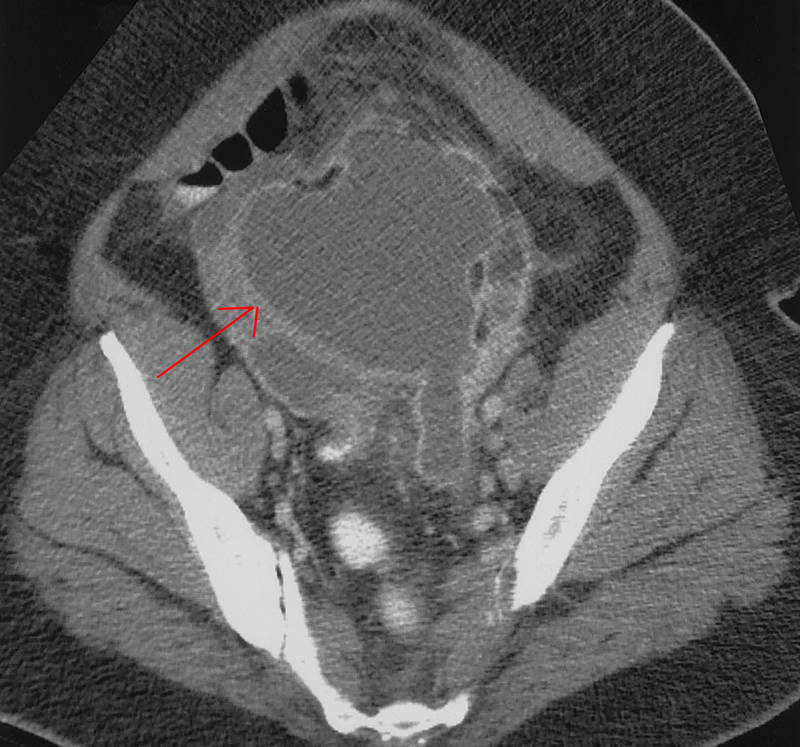

КТ диагностика тубоовариального абсцесса: Подходы и изображения

Раздел: Объективный взгляд